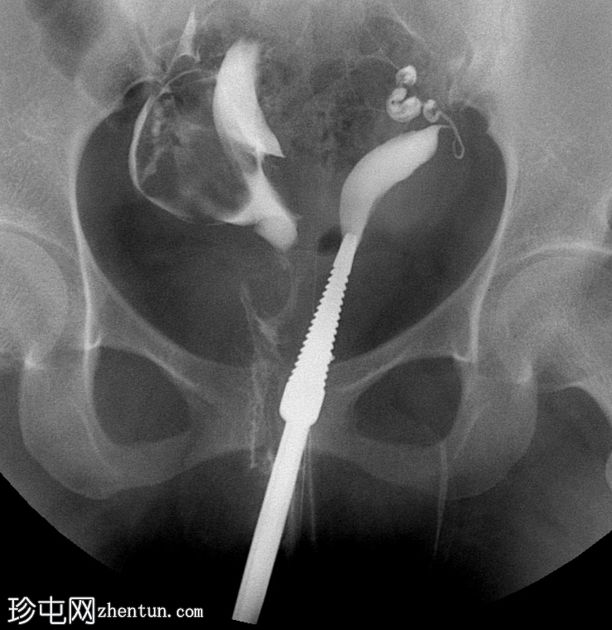

子宫输卵管造影

正位

2.jpeg

子宫输卵管造影显示两个独立的子宫腔,完全重复。可见两条独立的宫颈管。每个子宫角分别与其对应的输卵管相通。无统一的子宫底;子宫角明显分离。两个子宫腔均充盈并溢入腹腔。

子宫输卵管造影 (HSG) 显示两个间距较大的子宫腔和两个宫颈,强烈提示双子宫。

仅凭 HSG 可能不足以确诊——通常需要进一步影像学检查(MRI/三维超声)来评估子宫外轮廓并排除其他苗勒氏管畸形。